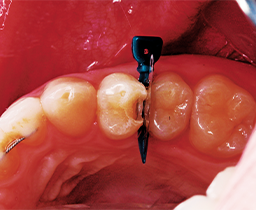

A 32 year-old female patient presented to the practice for her routine examination. The radiographs revealed primary lesions located interproximally (Fig. 1a). The patient was diagnosed with primary caries on tooth #5 DO (Fig. 1b). The clinical objective was to successfully remove caries and restore the tooth while delivering an optimal patient experience.

Fig. 1a Fig. 1b